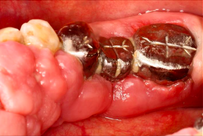

A 65-year-old female on antihypertensives and immunosuppressants presented with severe gum swelling, inability to chew, and difficulty maintaining oral hygiene. This led to multiple decayed and periodontally compromised teeth, worsening her overall condition.

- Non-surgical periodontal therapy was performed to reduce gingival inflammation and swelling

- Surgical removal of excessive gum tissues and extraction of multiple poor prognosis teeth were carried out as well

- She was kept under strict follow up and advised to comply with meticulous oral hygiene measures throughout treatment